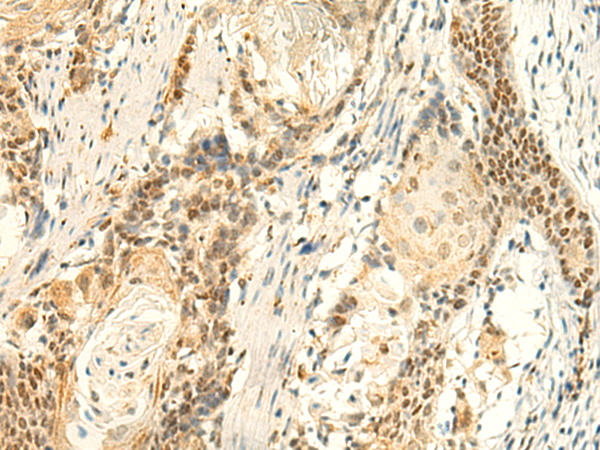

分类: 科研抗体货号: P10113别名: EIF2B; EIF-2Bbeta应用: IHC反应种属: Human, Mouse, Rat

分类: 科研抗体货号: P10090别名: RPC6; RPC39应用: WB,IHC反应种属: Human, Mouse, Rat

分类: 科研抗体货号: P10112别名: PUS4应用: IHC反应种属: Human, Mouse, Rat

分类: 科研抗体货号: P10089别名: ATPQ; ATP5H应用: WB,IHC反应种属: Human, Mouse

分类: 科研抗体货号: P10105别名: REGH; REGL; PSPS2; REGI-BETA应用: WB,IHC反应种属: Human

分类: 科研抗体货号: P10087别名: PNAA; PNAD应用: IHC反应种属: Human, Mouse

分类: 科研抗体货号: P10102别名: PFE; PTHR; PTHR1应用: IHC反应种属: Human, Mouse, Rat

分类: 科研抗体货号: P10086别名: NAPRT1; PP3856应用: IHC反应种属: Human

分类: 科研抗体货号: P10101别名:应用: WB,IHC反应种属: Human

分类: 科研抗体货号: P10085别名: HOT1; PBHNF; HNF1LA应用: WB,IHC反应种属: Human, Mouse